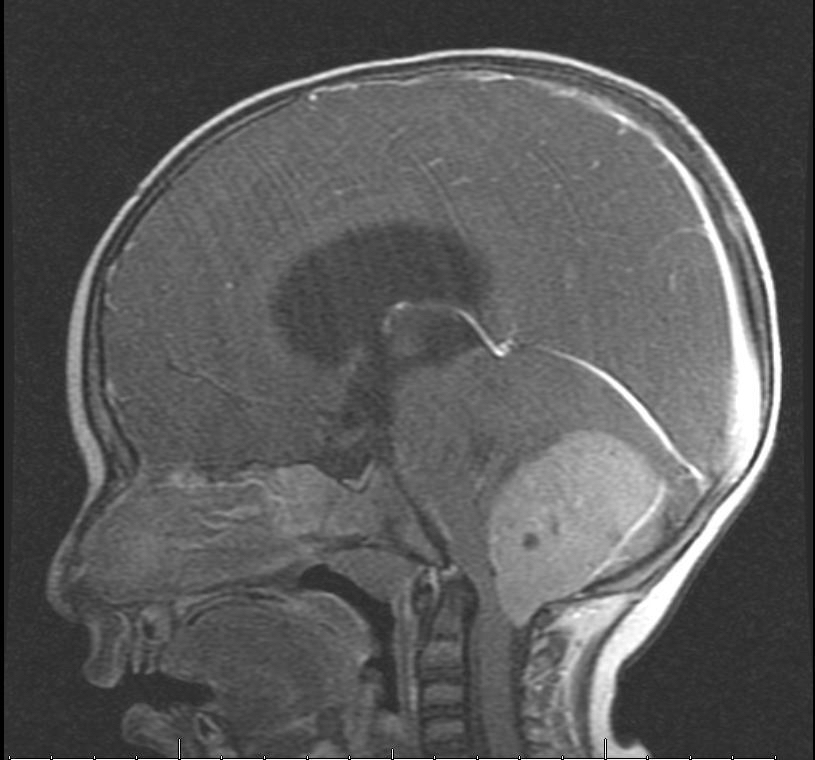

وأضافت: على الفور تم إجراء الفحص السريري والمخبري وأشعة مقطعية للرأس، والرنين المغناطيسي الذي بين وجود ورم كبير على شكل كتلة في منطقة المخيخ وتسببت له بضغط شديد على المراكز الحيوية في جذع الدماغ وأيضًا استسقاء دماغي شديد.

وأكد إجراء أشعة الرنين المغناطيسي لمنطقة الرأس مرة أخرى للتأكد من خلوه من أي بقايا لكتل ورمية، وبينت الأشعة سلامة المنطقة.